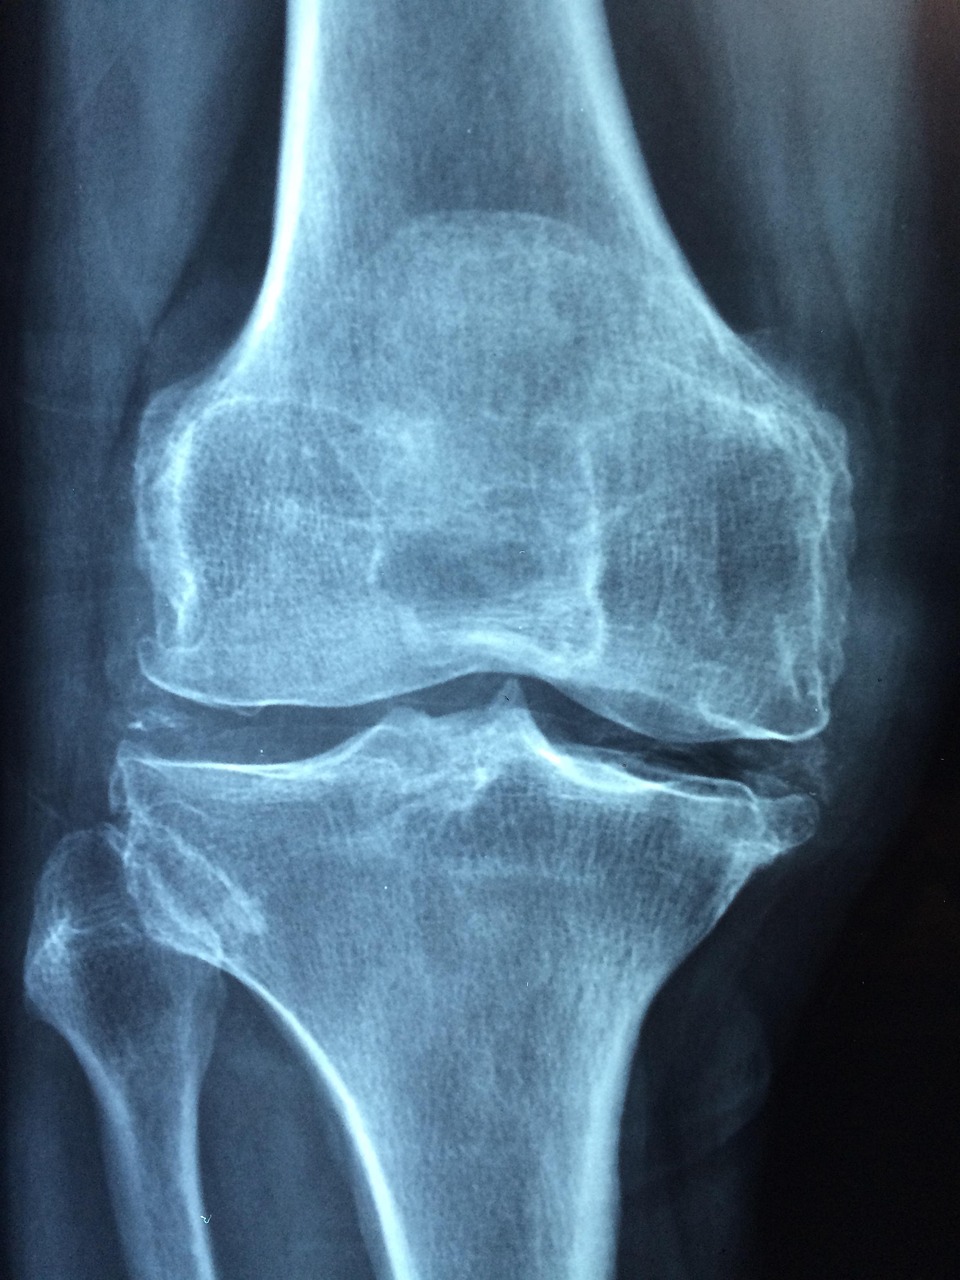

1. 골다공증은 완치가 가능한 질환일까?

의학적으로 골다공증은 “완치”보다는 “장기적인 관리”가 핵심인 질환입니다.

골밀도 수치를 일시적으로 올릴 수는 있지만, 나이와 호르몬, 유전적 요인에 따라 다시 낮아질 수 있기 때문입니다.

조기 치료와 지속적인 관리가 증상 악화를 막는 최선의 전략입니다.